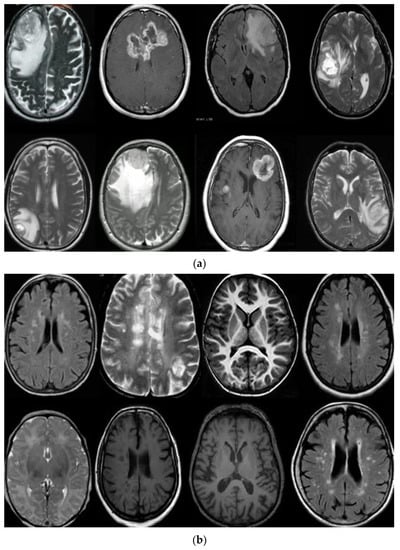

3. Datasets

- In classification, we applied a deep wavelet auto-encoder (DWAE) model. In this stage, the segmented MR brain image is resized by 256 × 256 × 1 dimension for faster processing. The objective of this stage is to predict the slices with tumor (abnormal MR brain images and the slices without tumor (normal MR brain images).